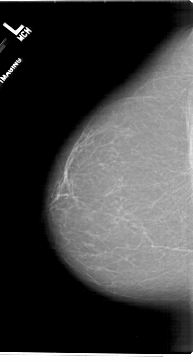

A_1716_1.LEFT_MLO

A_1716_1.LEFT_CC

LEFT_CC LINES 6871 PIXELS_PER_LINE 3661 BITS_PER_PIXEL 12 RESOLUTION 43.5 NON_OVERLAY

LEFT_MLO LINES 6541 PIXELS_PER_LINE 4081 BITS_PER_PIXEL 12 RESOLUTION 43.5 NON_OVERLAY